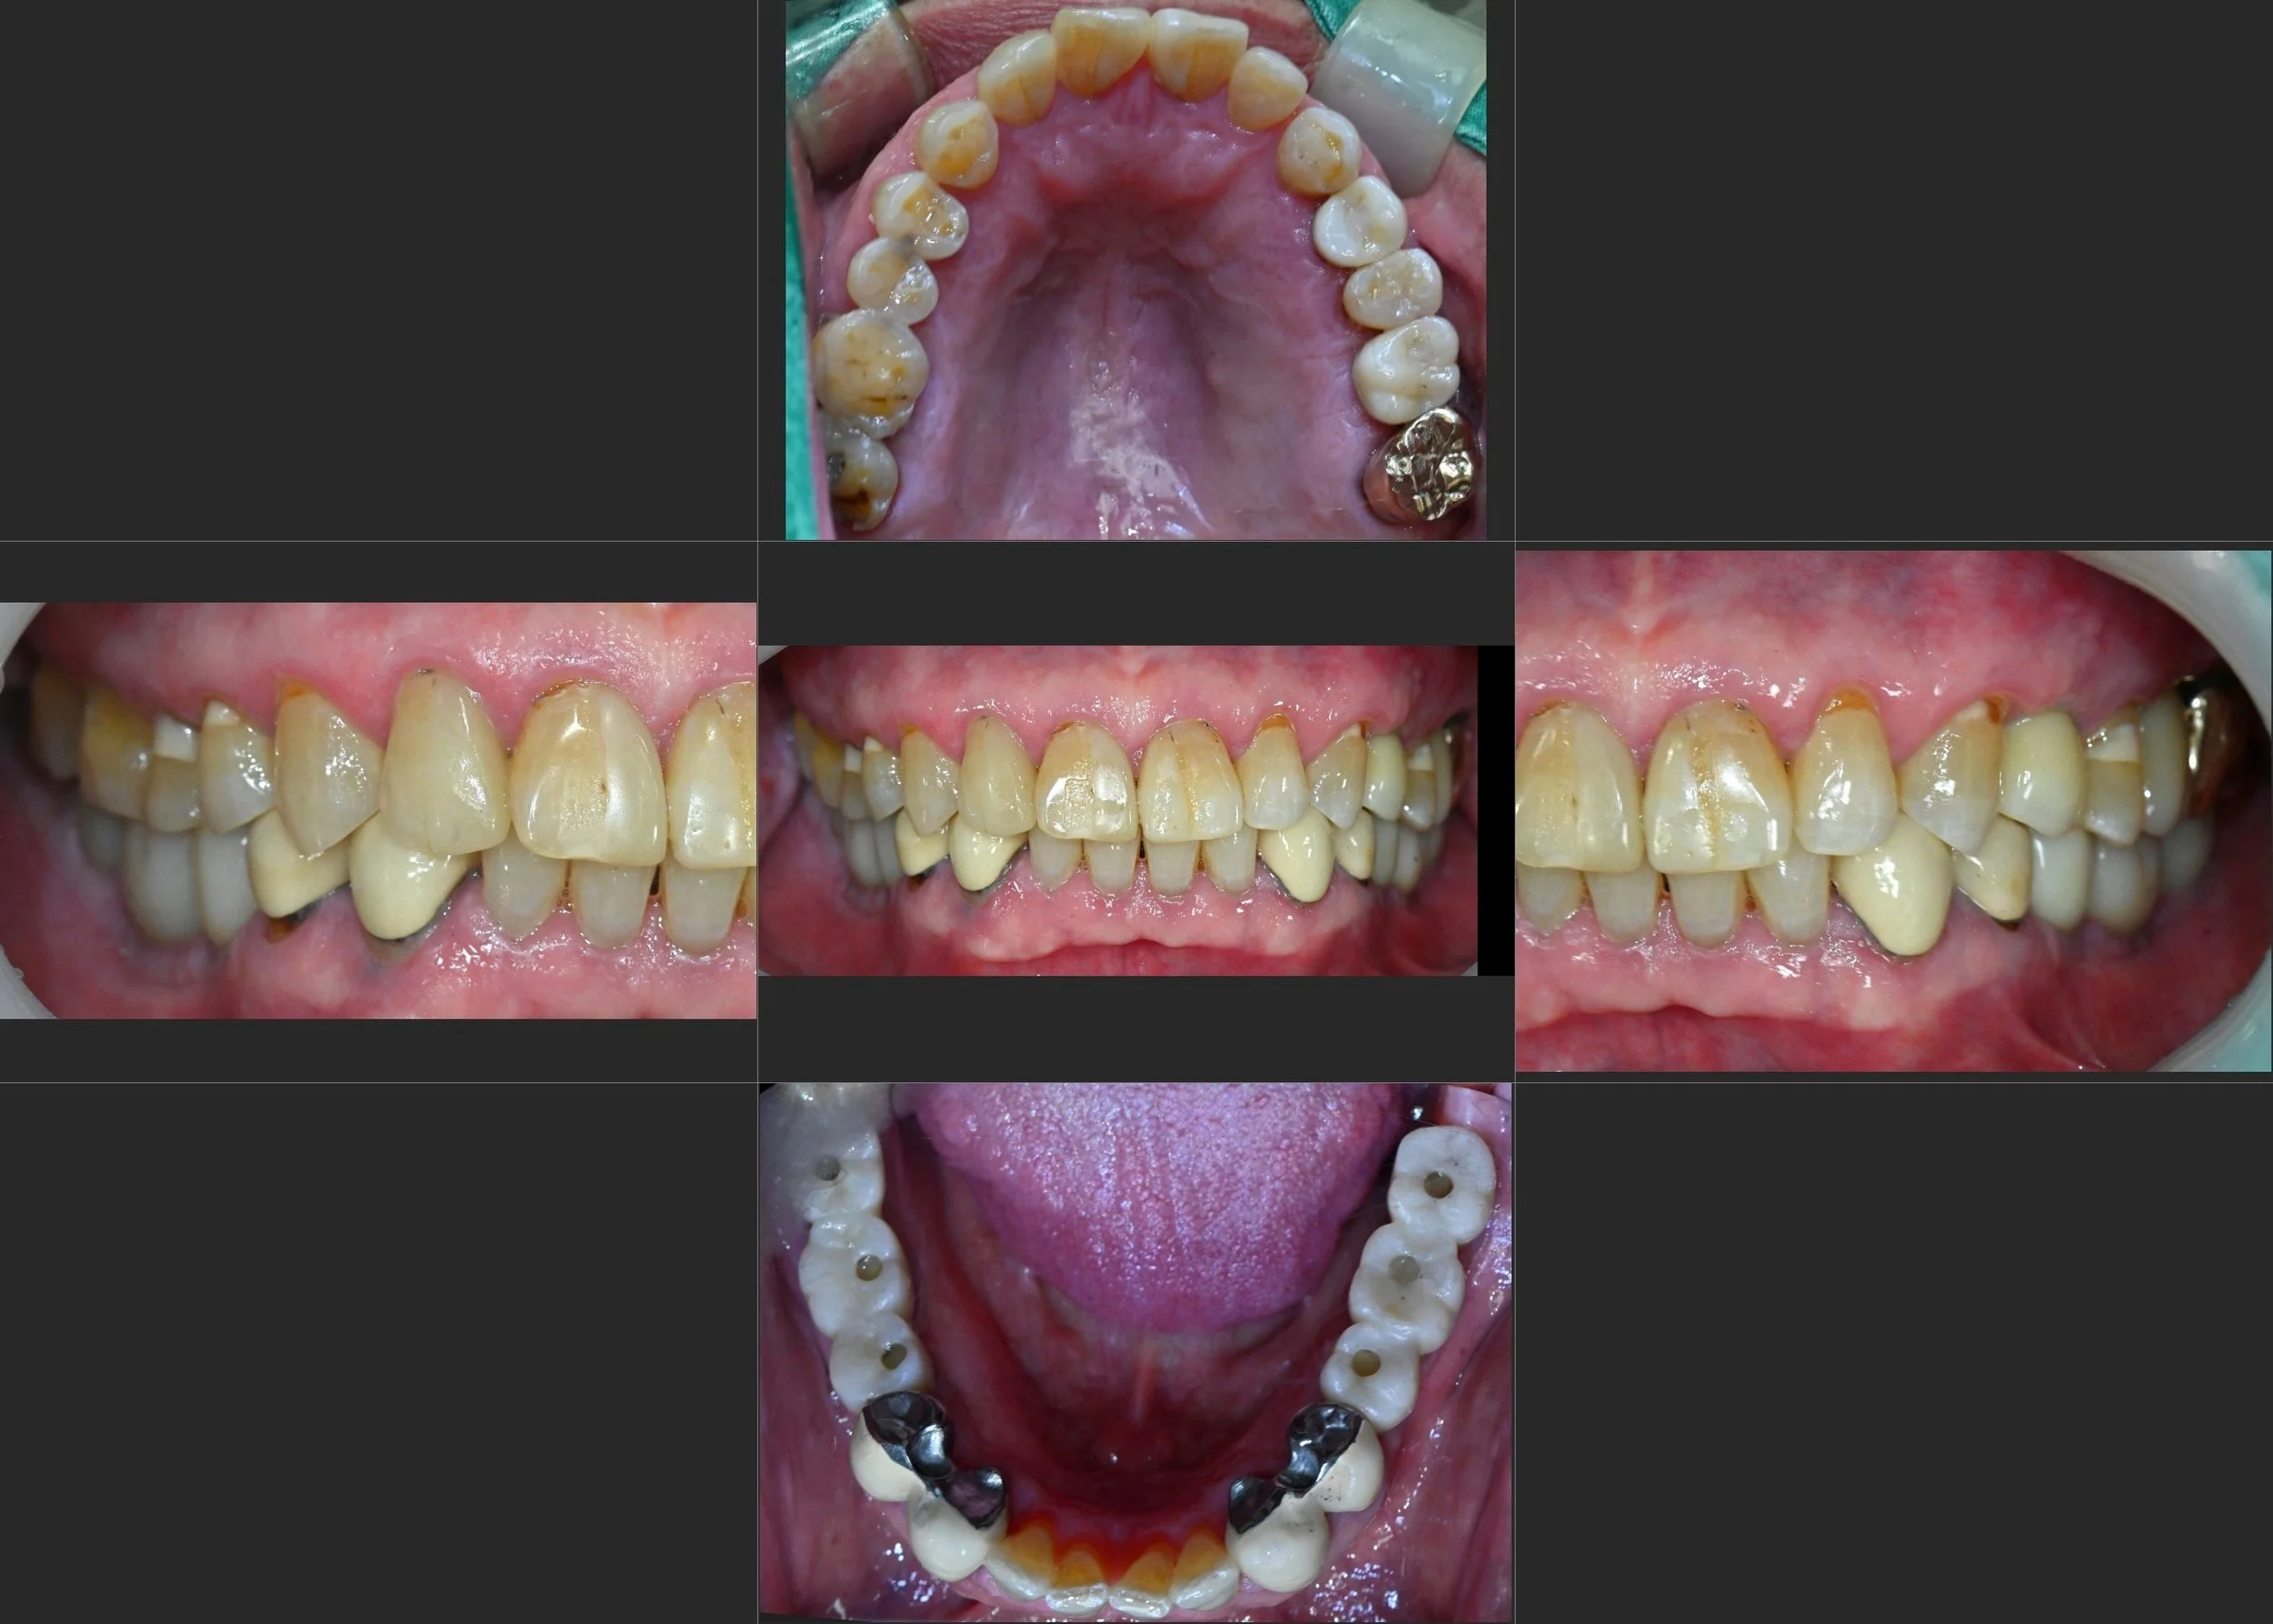

INTRA ORAL - AFTER

3. Phase 3: Anterior Refinement (Non-prep): Once the posterior stability was confirmed, the anterior spacing was addressed. To honor the patient's biological integrity, non-prep ceramic veneers were utilized. This approach allowed us to close the flared gaps and restore a youthful smile line without unnecessary tooth reduction.

4. Final Occlusal Calibration: The final restorations were delivered with a focus on mutual protection, ensuring that the posterior implants bear the load of mastication while the anterior veneers provide aesthetic harmony and proper guidance.

The result is a functional and aesthetic transformation that not only restored the patient's smile but also found the "sweet spot" of occlusal equilibrium.